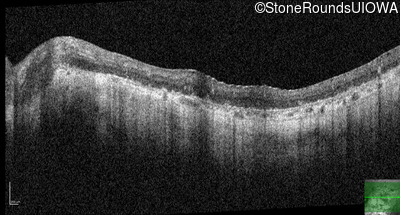

Optical Coherence Tomography - Right - Hand Motion sc

Exemplar / OCT Stack